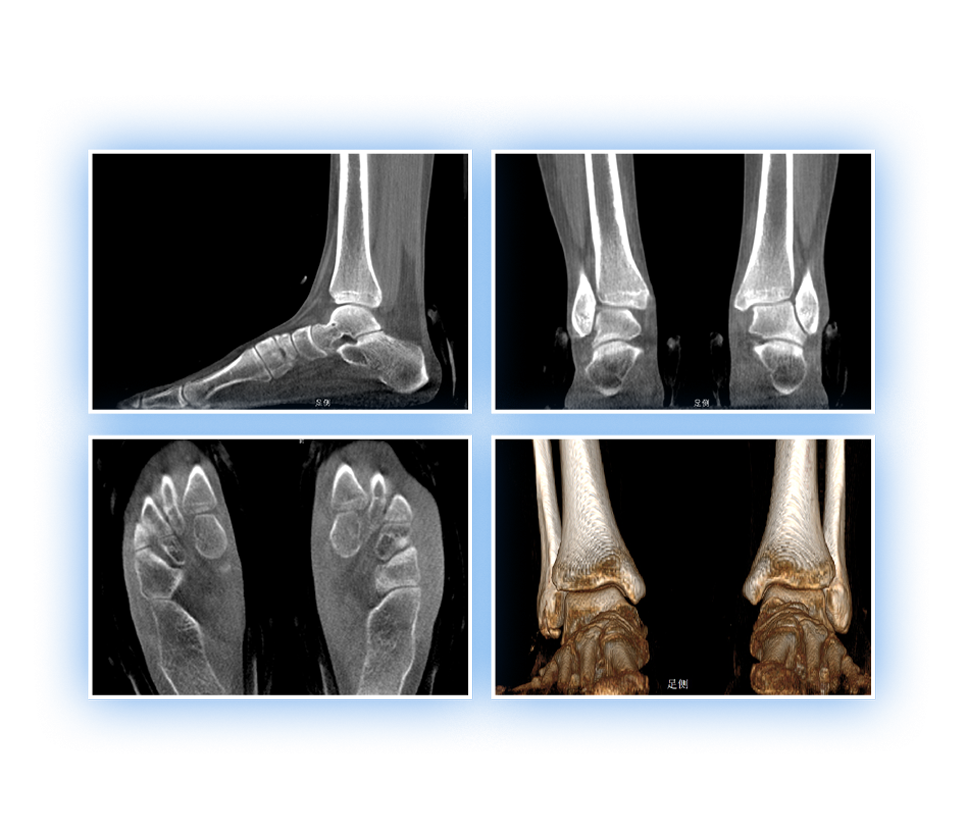

足踝

精准诊断

手术方案规划

术后随访